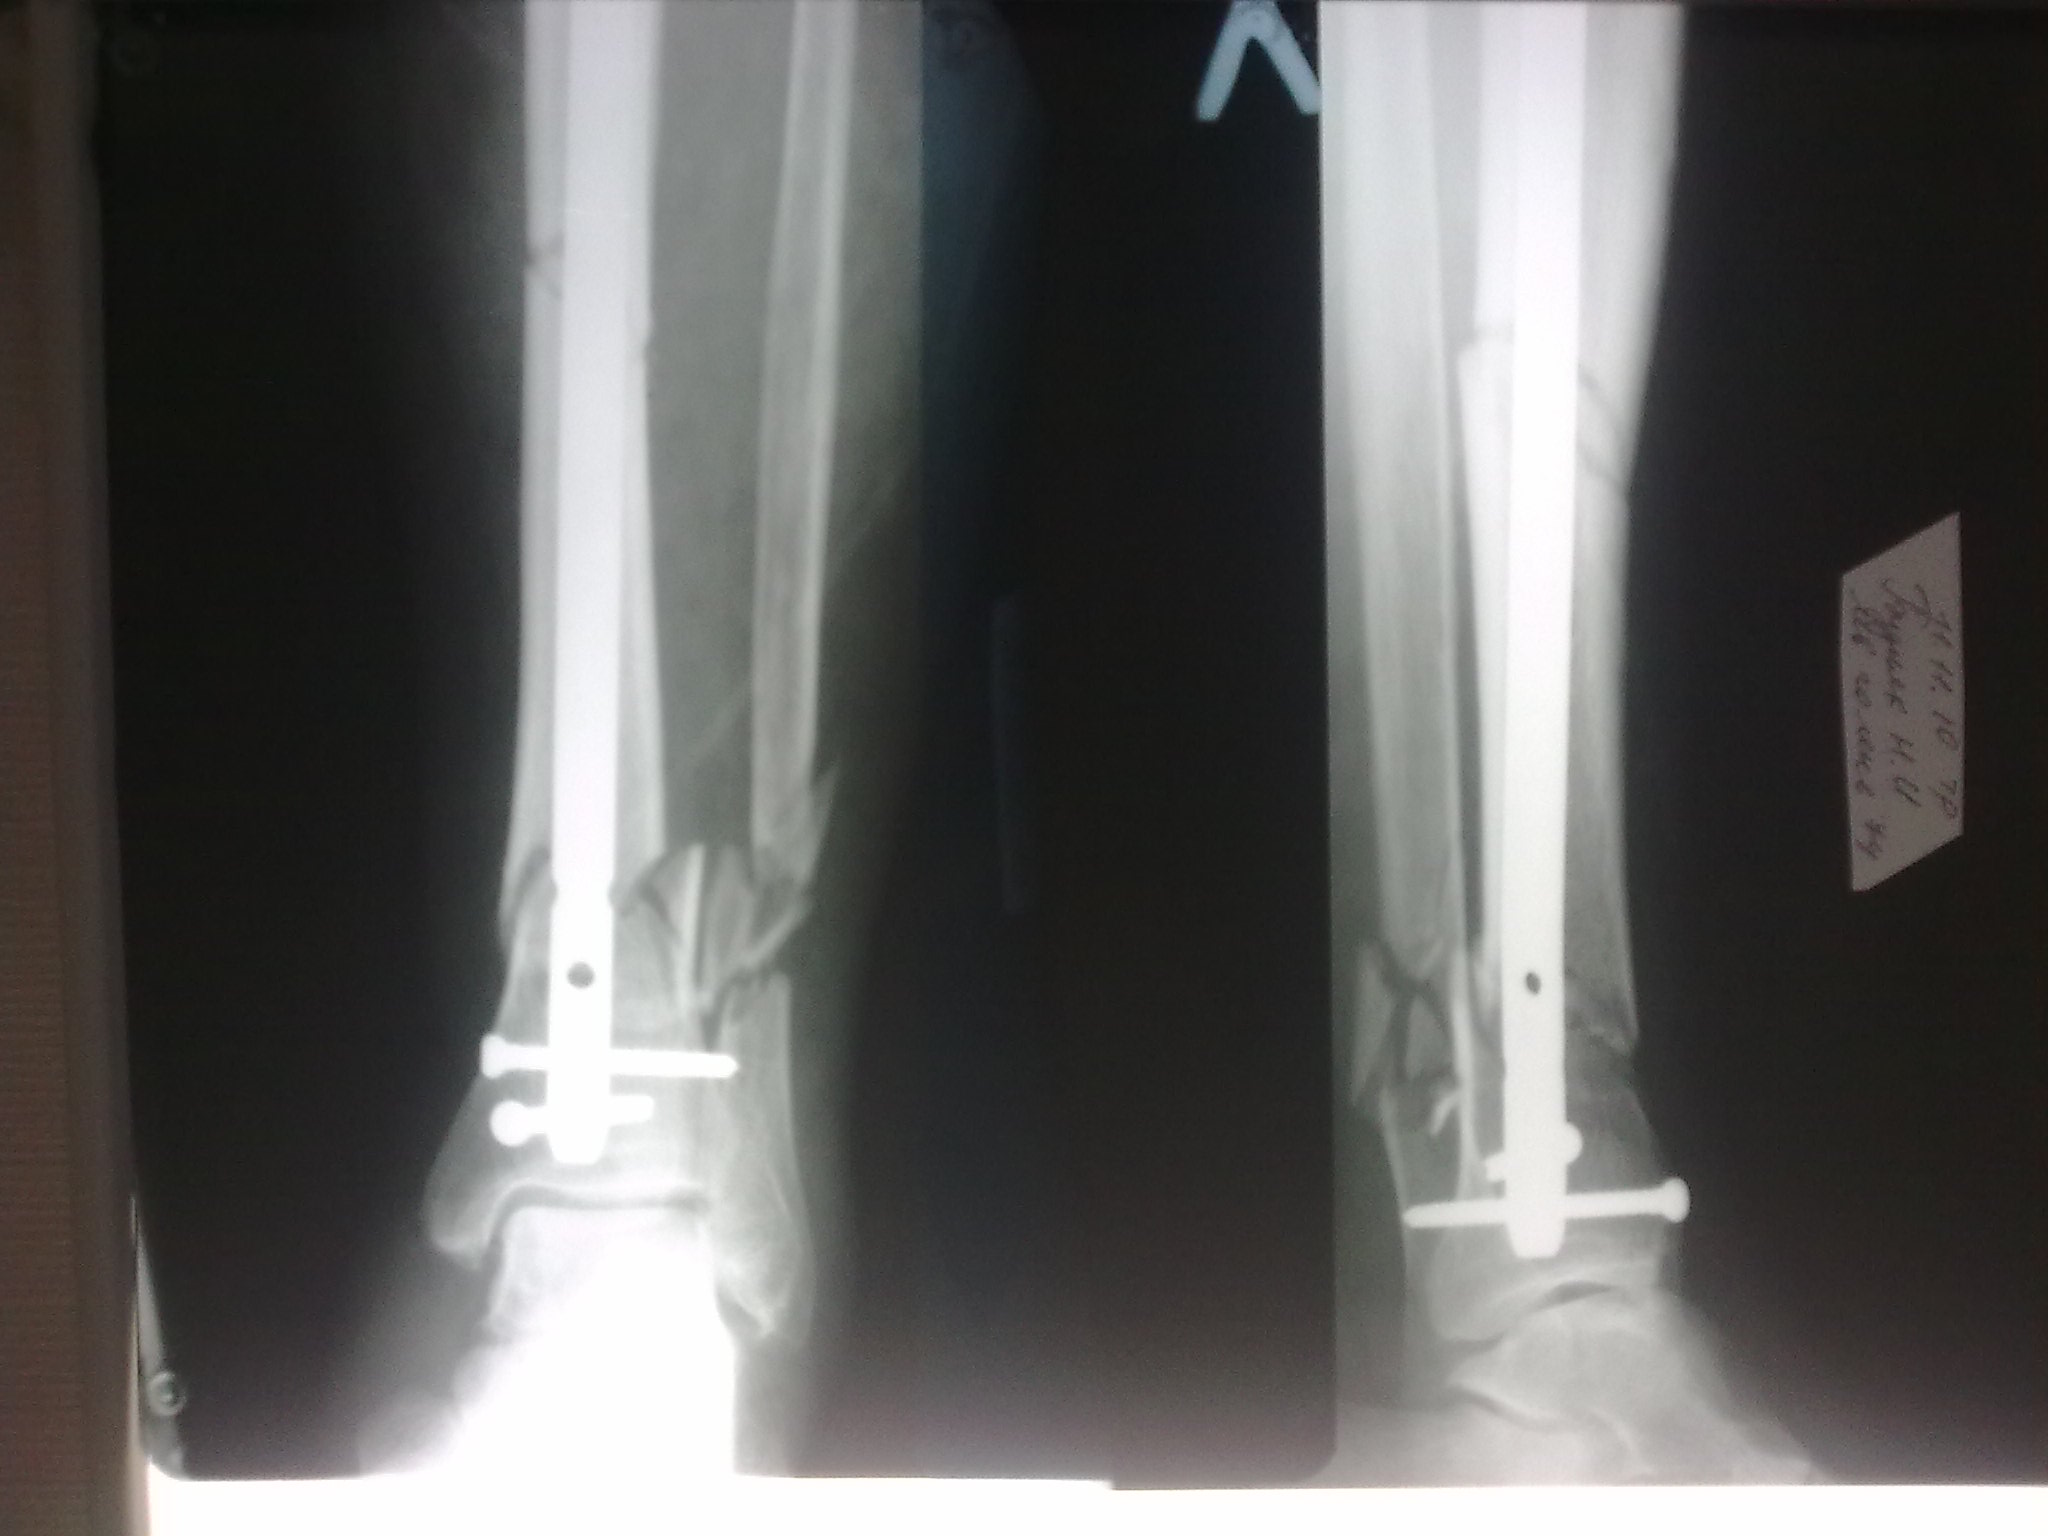

Уважаемые коллеги!БИОС занимаемся недавно. Хотелось бы услышать Ваше мнение па данному клиническому примеру. Пациенту 74 года.

Выполнен открытый БИОС, обнаружен выраженный остеопороз, один из проксимальных винтов(самый верхний) и один из дистальных (нижний) "сорвались". В средней трети - косо-поперечный перелом (на фото не захвачен) с хорошей репозицией. Клинически фиксация переломов стабильна. Выполнить МОС малоберцовой кости не представлялось возможным из-за фликтен по латеральной поверхности голени.

4. Диаметр стержня - 11, нержавейка, производитель Санатметалл

можно посмотреть рнтгенограммы всего сегмента с захватом коленного и голеностопного суставов?